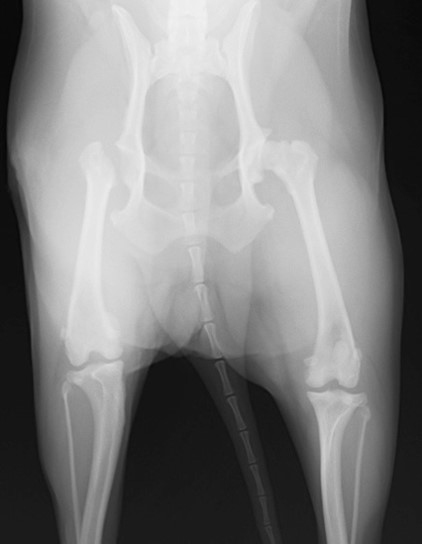

眼球摘出、眼瞼腫瘤切除、チェリーアイ整復、眼瞼縫合、瞬膜フラップ、眼球突出整復、耳介切除、垂直耳道切除、総耳道切除、鼻鏡切除、口腔腫瘍切除(上顎骨切除、下顎骨切除を含む)、各種抜歯(猫の全臼歯抜歯含む)舌腫瘍切除、唾液腺嚢胞切除、皮膚腫瘤切除、断脚(前肢、後肢、片側骨盤切除)、断尾、肺葉切除、胸腺腫切除、心膜切除、横隔膜ヘルニア整復、肝臓腫瘍切除、胆嚢摘出、胃切開、胃拡張胃捻転症候群整復、胃腫瘍切除、腸管切開、腸管腫瘍切除、直腸腫瘍切除(粘膜、全層プルスルーなど)、腎臓摘出、SUB設置手術、脾臓摘出、副腎摘出、膀胱切開、膀胱腫瘍切除(部分切除、全摘出、膀胱尿道一括切除など)、卵巣腫瘍切除、精巣腫瘍切除、卵巣子宮全摘出、肛門嚢切除、各種骨折、膝蓋骨脱臼整復、股関節脱臼整復、大腿骨頭切除、椎間板ヘルニア(各種椎弓切除術)、各種リンパ節切除 など